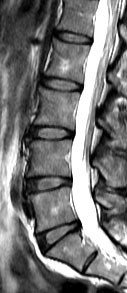

今次的研究是一項以南中國地區人口而作出的具代表性抽樣研究,從上述大型人口群組中抽出21歲或以上的成年人為研究對象。在是次的研究中,研究人員分析了合共2,599位成年人的磁力共振(MRI)檢查數據。當中27%(709人)沒有椎間盤退化,而73%(1,809人)則有椎間盤退化。在患有椎間盤退化的成年人當中,有7%體重過輕,48%體重正常,36%過重和9%肥胖。超重及肥胖的成年人出現椎間盤退化程度及發展成更嚴重的病徵的機會,比正常體重或過輕的成年人嚴重。